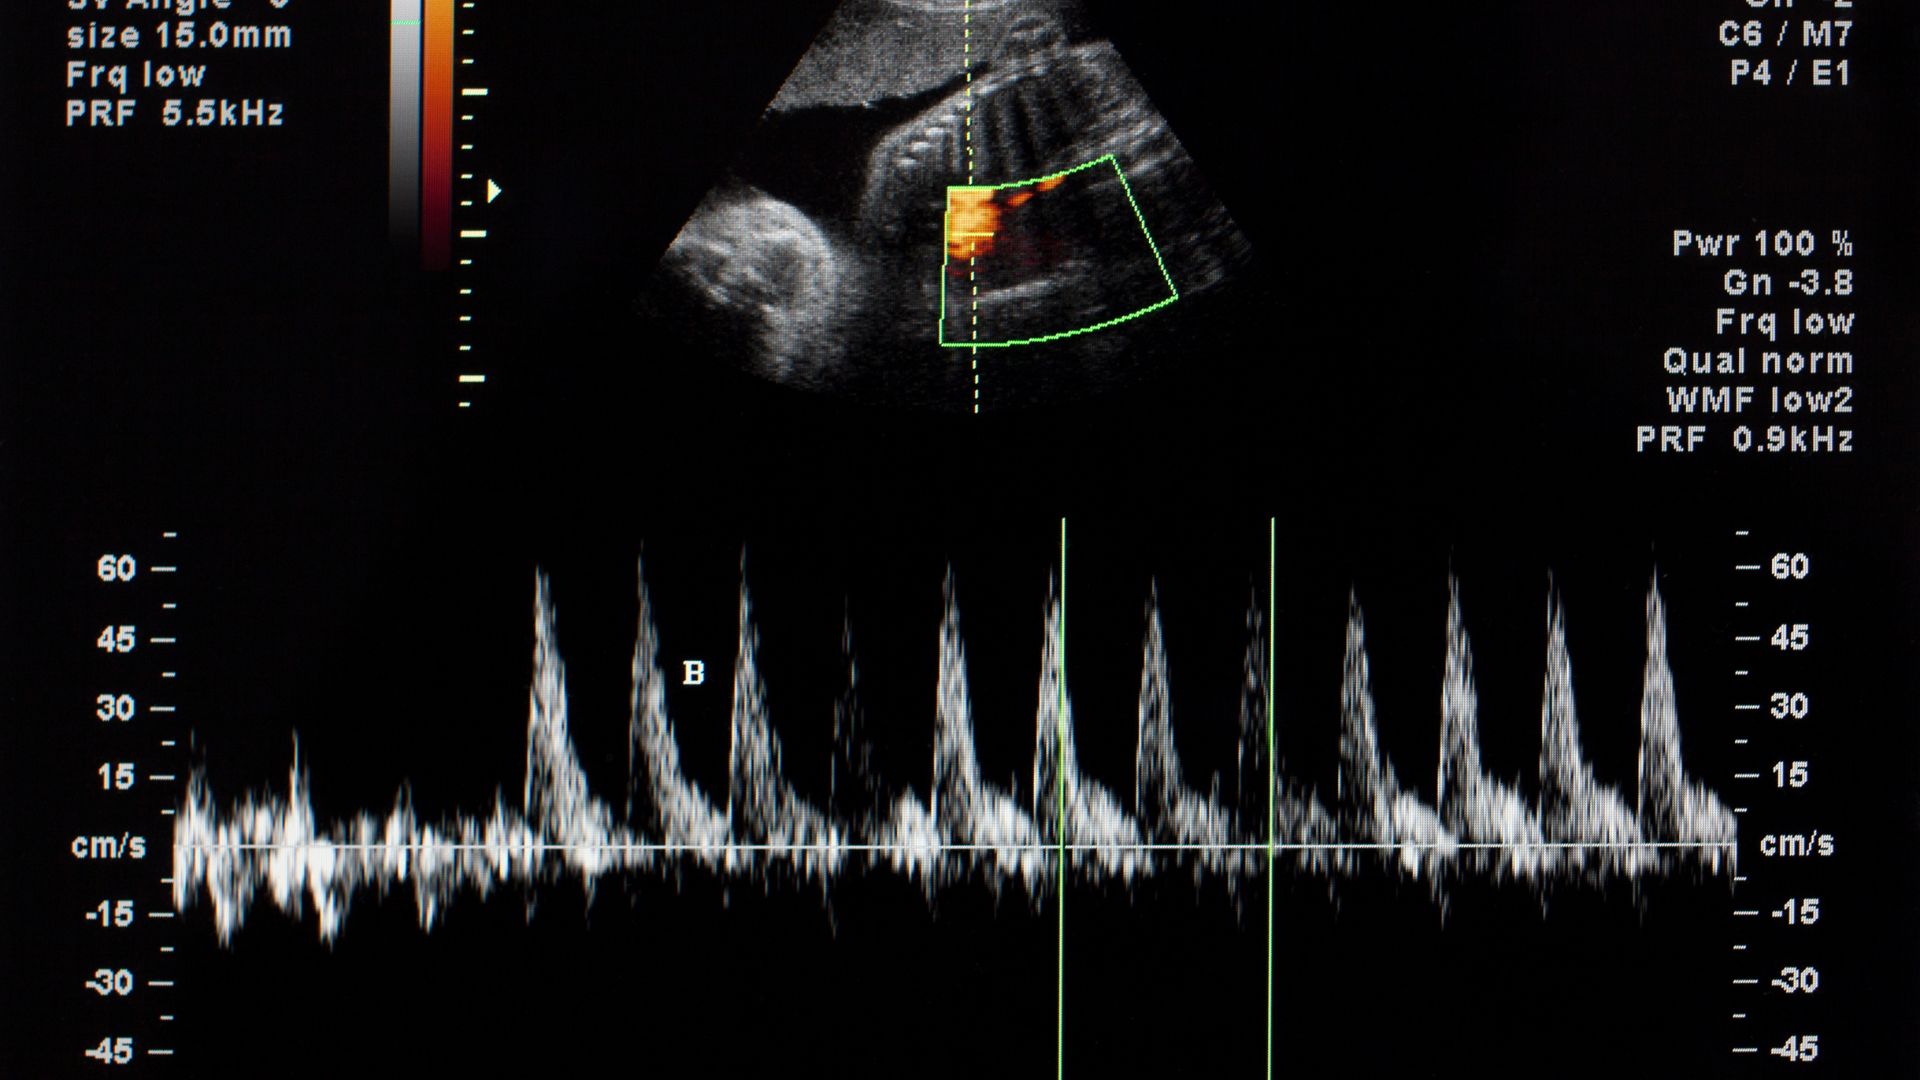

Tim thai bắt đầu hình thành vào khoảng tuần thứ 6 của thai kỳ. Khi siêu âm, bác sĩ có thể quan sát được những điểm sáng lấp nháy tượng trưng cho hoạt động tim thai. Lúc này, nhịp tim thường dao động từ 90 đến 110 nhịp mỗi phút và sẽ tăng dần theo từng ngày. Đến khoảng tuần thứ 9, nhịp tim thai đạt mức cao nhất, từ 140 đến 170 bpm, con số này xuất hiện ở cả thai nam lẫn thai nữ. Do đó, bạn không thể biết được giới tính của thai nhi qua nhịp tim.

Tuy nhiên, đây chỉ là suy đoán dân gian, không dựa trên bất kỳ cơ sở khoa học nào nên không thể khẳng định tính chính xác. Theo các bác sĩ chuyên khoa, nhịp tim của thai nhi thay đổi tùy vào từng giai đoạn trong thai kỳ. Trong những tuần đầu, khi tim thai mới hình thành, nhịp tim thường cao. Vào giữa thai kỳ, chỉ số này có xu hướng giảm dần và đến cuối thai kỳ sẽ ổn định trong khoảng từ 120 đến 160 nhịp/phút.

Ngoài ra, nhịp tim nhanh hay chậm còn phụ thuộc vào nhiều yếu tố khác nhau như tình trạng vận động của thai nhi, sức khỏe của mẹ, hoặc thậm chí là thói quen ăn uống và nghỉ ngơi của mẹ bầu. Chính vì vậy, nhịp tim thai là một chỉ số quan trọng dùng để theo dõi sức khỏe, chứ không phải là căn cứ xác định giới tính.